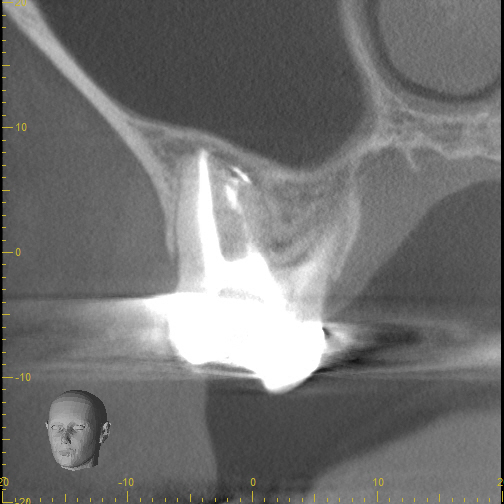

3_pre CBCT

8_recall 1 yr CBCT

Case 7

These images are from a 3D scan and show how important is a correct diagnosis. The pre-treatment image on the left shows what looks like two teeth with infections, but thorough testing showed that only one tooth needed treatment. The right image shows complete healing--around both teeth-- one year later. A careful diagnosis resulted in saving the adjacent tooth from unneeded treatment.